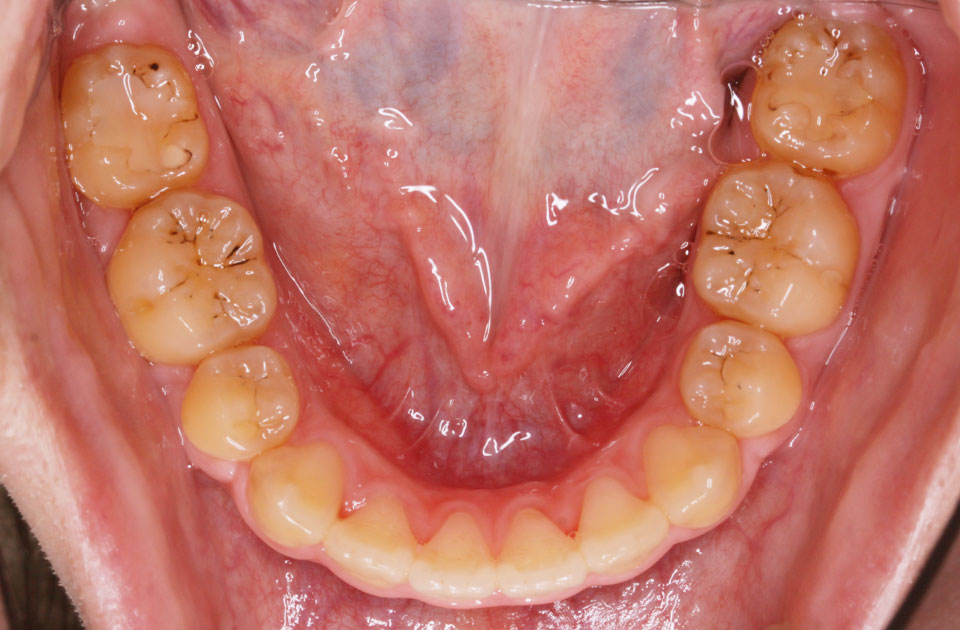

矯正後 下顎

矯正前 下顎